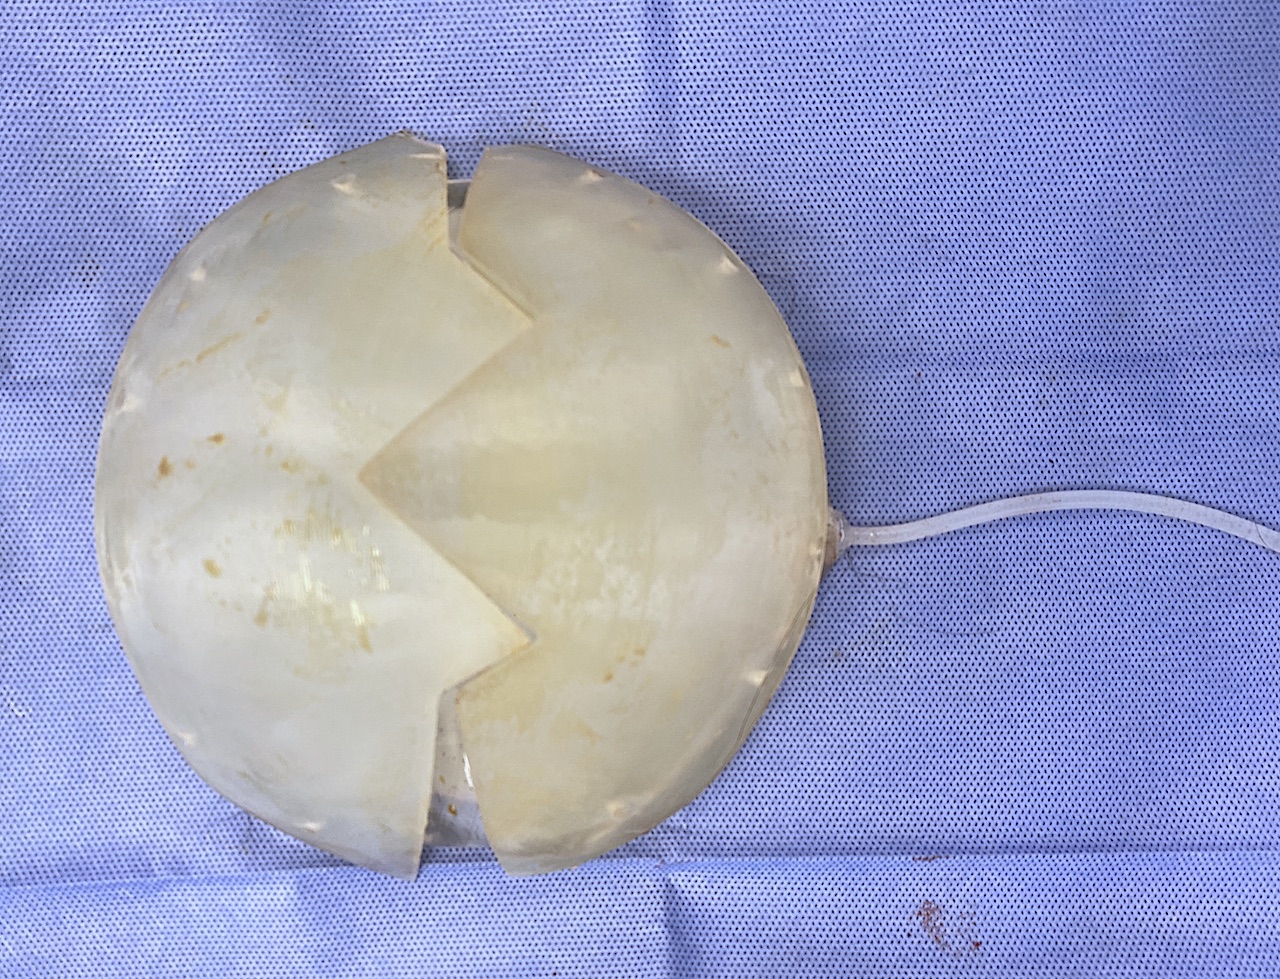

Desire for augmentation of congenitally flat back of head. The amount of implant volume needed was determined by an implant design of 200ccs. This required a first stage scalp expansion.

A scalp tissue expander was initially placed and the patient successfully inflated it over three months to 190ccs. It was removed and replaced thereafter with a large back of the head skull implant.

Desire for augmentation of congenitally flat back of head. The amount of implant volume needed was determined by an implant design of 200ccs. This required a first stage scalp expansion.

A scalp tissue expander was initially placed and the patient successfully inflated it over three months to 190ccs. It was removed and replaced thereafter with a large back of the head skull implant.